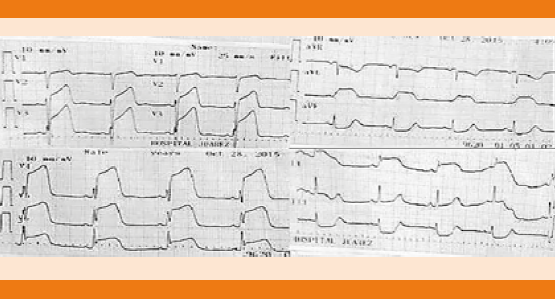

Paciente femenina de 68 años de edad, con antecedente de hipertensión arterial sistémica y cirugía de clipaje por hemorragia subaracnoidea 14 años antes. Ingresó por pérdida del estado de alerta, crisis convulsivas tónico-clónicas generalizadas y deterioro neurológico con puntaje de acuerdo con la escala de coma de Glasgow de seis puntos a expensas de: respuesta ocular: un punto, respuesta verbal: dos puntos y respuesta motora: tres puntos, de 12 horas de evolución. A su ingreso en el servicio de Urgencias se decidió dar manejo avanzado de la vía aérea, vasopresor e inotrópicos, así como cuidados de paciente neurocrítico. La tomografía de cráneo simple evidenció imagen hipodensa en la región frontotemporal derecha sugerente de infarto que correspondía al territorio de la arteria cerebral media derecha y cambios posquirúrgicos asociados (Figura 1). El electrocardiograma de 12 derivaciones mostró desnivel positivo en la cara anterior extensa, lesión subepicárdica en la cara anterolateral extensa, desnivel negativo en la cara inferior, lesión subendocárdica inferior, sin datos de isquemia o necrosis (Figura 2). Biomarcadores de lesión cardiaca: troponina 2.1, CK 232, CK-MB 33. Por los cambios encontrados en el electrocardiograma y el incremento de biomarcadores cardiacos se realizó coronariografía en la fase aguda para excluir oclusión coronaria que reportó ausencia de lesiones estenóticas o placas de ateromas en la circulación coronaria derecha e izquierda. En los ventriculogramas se observó dilatación apical fija e hipocinesia con movilidad conservada en las bases. Insuficiencia mitral leve. Presión telediastólica del ventrículo izquierdo de 18 mmHg y fracción de eyección del ventrículo izquierdo de 40% (Figura 3). El desenlace de la paciente lamentablemente fue funesto.

Figura 2 Electrocardiograma de 12 derivaciones, a velocidad de 25 mm/seg, ritmo sinusal, intervalo R-R regular, frecuencia cardiaca 65 latidos por minuto, QRS 80 mseg, PR 160 mseg, QT 200 mseg, desnivel positivo en la cara anterior extensa, lesión subepicárdica en la cara anterolateral extensa, desnivel negativo en cara inferior, lesión subendocárdica inferior, sin observarse datos de isquemia o necrosis.